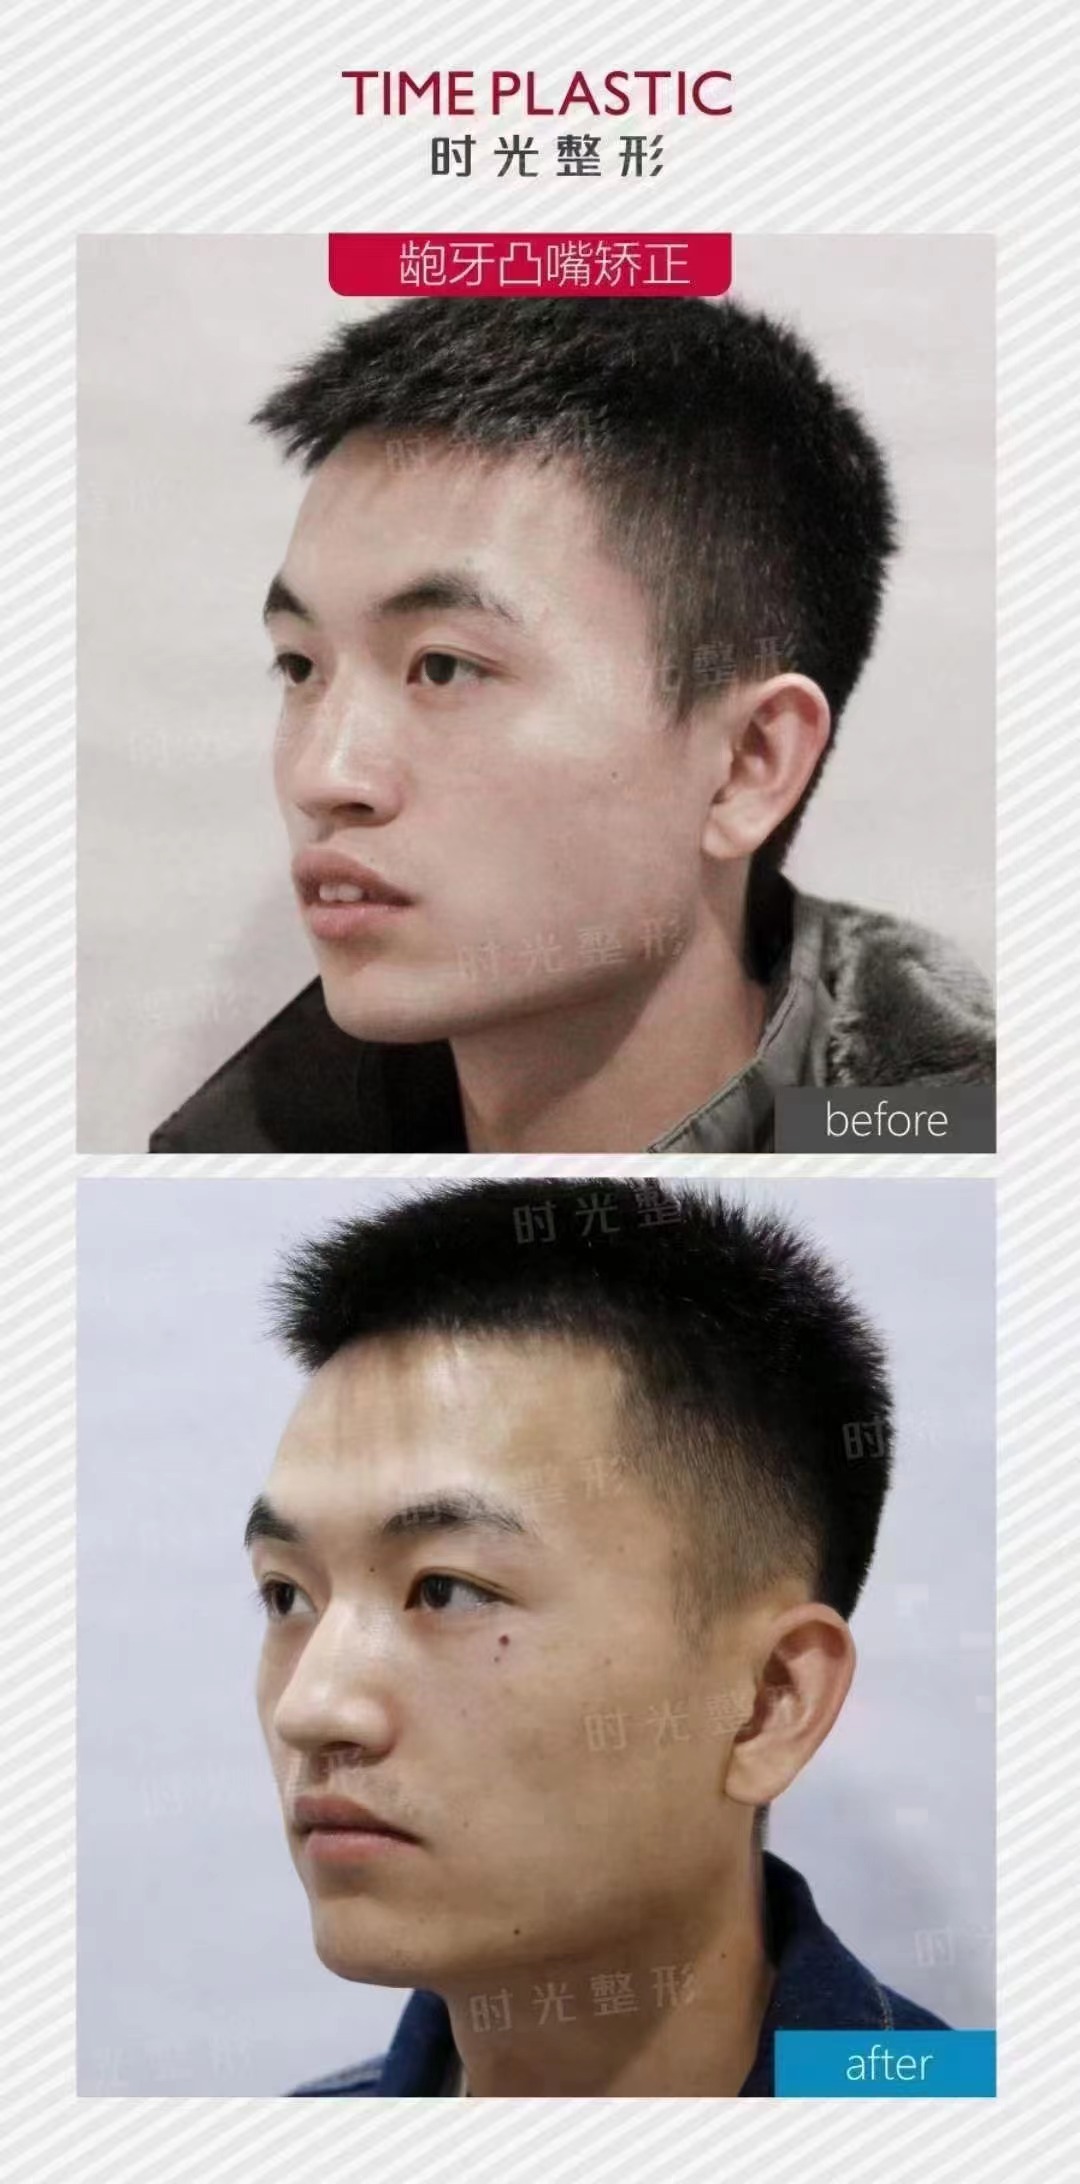

2、南宁岭南口腔牙齿矫正收费标准

南宁岭南口腔金属托槽矫正价格12000元起

南宁岭南口腔隐形矫正价格18000元起

南宁岭南口腔时代天使隐形矫正价格30000元起

南宁岭南口腔隐适美隐形矫正价格42000元起

南宁岭南口腔做牙齿矫正也是很不错的,技术比较先进,价格在12000~42000元不等,能够帮助患者选择合适的牙套,他们家矫正牙齿的时间比较短,医生的技术比较好,患者口腔内的压力不会过大,而且矫正力度比较大,医生审美也很不错,矫正之后的牙齿比较整齐,同时也对口腔功能进行了修复。